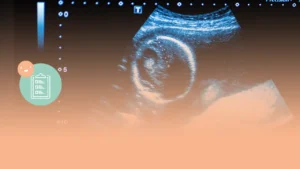

Ecografía 5 semanas: Descubre el desarrollo temprano del embrión

La ecografía en la quinta semana de embarazo permite conocer el desarrollo temprano del embrión. Durante esta etapa, se puede medir su tamaño y detectar